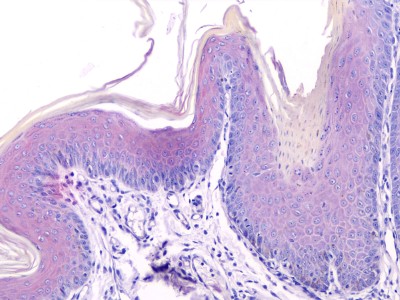

Photo 11 : Hyperkératose ortho et parakératosique, absence de dégénérescence vacuolaire des kératinocytes basaux (HES, x 200)

Photo 12 : Grains de kératohyaline de taille et de forme irrégulières (HES, x 400,)

L’examen histologique confime l’hyperkératose parakératosique en nappe, essentiellement infundibulaire. Les cellules parakératosiques sont arrondies et se détachent une par une, sans perdre leur forme.

On constate également une hyperplasie épidermique et une papillomatose, et l’absence de dégénérescence vacuolaire des kératinocytes basaux.

L’examen ultrastructural (en microcopie électronique) montre une couche cornée très épaisse, et la présence de très nombreux grains de kératohyaline dans les kératinocytes de la couche cornée.

Les ichtyoses épidermolytiques sont les seules caractérisées par un véritable trouble de la kératinisation. L’anomalie génétique est une mutation des kératines, qui entraine une anomalie du cytosquelette, à l’origine des lésions microscopiques. Les kératinocytes des couches granuleuse et épineuse superficielle sont fragilisés, se vacuolisent avec des grains de kératohyaline de grande taille, et se lysent, entrainant la formation de vésicule. Une hyperkératose s’installe.